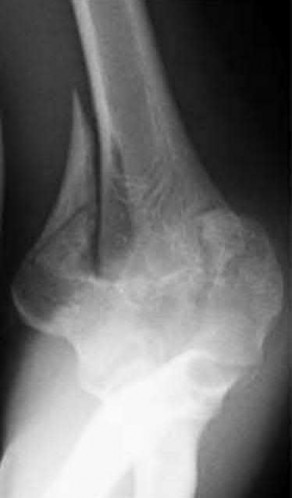

A 24-year-old woman is thrown from her motorcycle and sustains the closed injury shown in Figures A through C. Open reduction and internal fixation is planned. What surgical technique will best allow visualization of the joint surface and allow early range of motion?

1) Bryan-Morrey approach and parallel plating

2) Triceps reflecting anconeus pedicle approach and parallel plating

3) Triceps reflecting anconeus pedicle approach and orthogonal plating on the posteromedial and lateral surfaces

4) Olecranon osteotomy and parallel plating

5) Olecranon osteotomy and orthogonal plating on the posteromedial and lateral surfaces

Access to complex intra-articular fractures is best achieved by an olecranon osteotomy (OO). Fixation can be with parallel plating or orthogonal plating.

Bicolumnar fixation of distal humerus fractures should follow the principles outlined by O'Driscoll: Distal fragments should be held by as many screws as possible; every screw in the distal fragments should pass through a plate; each screw should engage as many articular fragments as possible.

Galano et al. review treatment for bicolumnar distal humerus fractures. They note that the olecranon osteotomy, Alonso-Llames triceps sparing and Campbell triceps splitting approaches expose 57%, 46% and 35% of the articular surface, respectively. The OO and paratricipital (triceps sparing)

approaches allow for early ROM. Protected motion is required for the O'Driscoll TRAP and Bryan-Morrey approaches for tendon-to-bone healing.

Coles et al. retrospectively reviewed the OO in fixation of 70 fractures. Osteotomy fixation was with an intramedullary screw and dorsal ulnar wiring, or with a plate. The rate of OO increased with fracture difficulty (from AO type C1-C3). There was 1 delayed union but no nonunions.

Figures A and B show a AO/OTA type C2 intraarticular distal humerus fracture. Figure C is a coronal CT scan showing intraarticular comminution. Illustration A shows fixation of the fracture with bicolumnar plating through an olecranon osteotomy approach. Illustration B shows the various approaches to the distal humerus (left, Campbell triceps splitting; center left, O'Driscoll triceps reflecting anconeus pedicle; center right, Bryan-Morrey approach, leaving the triceps attached laterally to the fasciocutaneous flap, but elevating it off the ulna; right, olecranon osteotomy). Illustration C shows 3 methods of olecranon osteotomy (A and B, Intra-articular transverse; C-F, Extra-articular oblique; G, Intra-articular chevron).